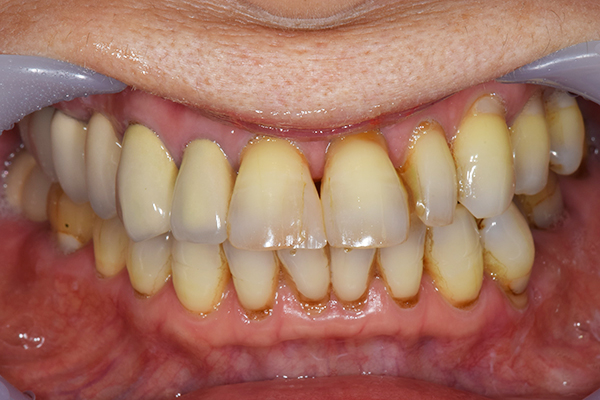

前歯が折れて当院にいらっしゃいました。 過去に下の入れ歯を作ったが、合わなくなってずっと入れ歯をいれていらっしゃらない患者様でした。 これは奥歯で噛むことができないため、前歯で噛むことを繰り返したために、負担に耐えられなくなった前歯が折れてかぶせ物ごと 外れてしまったのだと考えられます。 痛くない、違和感の少ない、下の入れ歯を作ることがこの方のゴールであると考えられました。

治療方針 長年使ってきた義歯の人工歯が磨耗し、臼歯部での咬合がすくなくなり、前歯部での接触が強くなったことで生じた前歯の破折なので、義歯も作り変える必要がある。

治療内容 前歯部MTMと同時に審美面の回復。

MTM中に義歯の作成も同時に行う。

最終的に義歯と前歯のクラウンを同時にいれる。

義歯は下顎で、しっかり噛めること、違和感の少ないものという希望があったため、なるべく入れ歯を薄く作成するために金属をしようした義歯とした。

また、見た目もあまり義歯が目立たない様に、バネの部分を見えにくいように作成した。